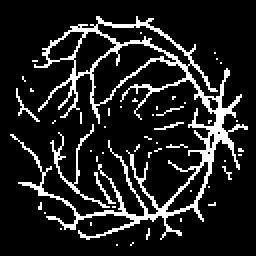

Vessel Extraction

Experiments are implemented on the Digital Retinal Images for Vessel Extraction database (DRIVE) proposed for studies on the extraction of blood vessels (Staal et al. 2004). Models are trained after reshaping all data at 256256 size. Rand score and information theoretic score is also used as evaluation metrics.